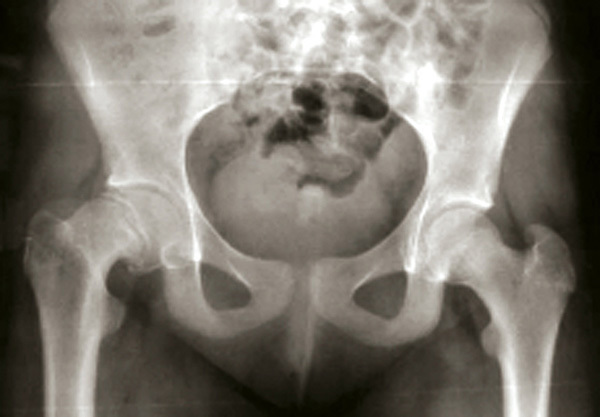

Epiphysiolyse de hanche droite chronique ou stable

L'épiphyse fémorale droite apparaît basculée vers le bas comparée au côté gauche.